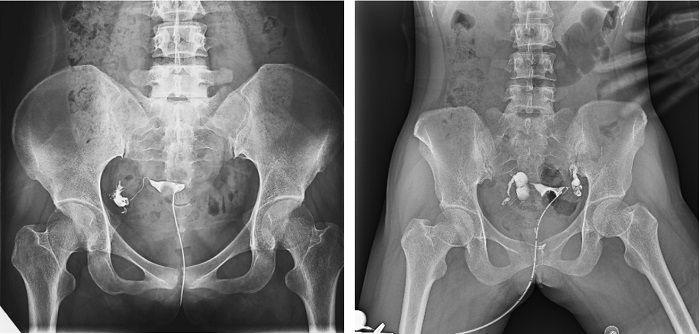

子宮輸卵管造影檢查損傷小,準確率高,是婦科檢查的常用方法。利用動態DRF進行子宮輸卵管造影檢查,大大超越了過去的檢查技術,更加精準高效。動態DRF矩形采集面積大,一次曝光即可顯示整個盆腔,大幅減少觀察時間,可控的瞬時照射避免受檢者吸收過多X線,對育齡期女性檢查尤為重要??稍谠煊皠┝鲃拥倪^程中完成拍片,抓拍到關鍵圖像,幫助醫生更加清楚地了解到管腔的具體通暢情況及堵塞部位,提高診斷的精準性。

▲輸卵管造影

普利德動態平板DRF床體智能化程度更高,在進行子宮輸卵管造影檢查時,醫生可以通過調整床體起倒角度精準控制造影劑的流動方向和速度,并根據造影劑在輸卵管及盆腔里的顯影準確判斷輸卵管堵塞部位、程度及性質,極大提高了拍片效率和診斷的精準性。